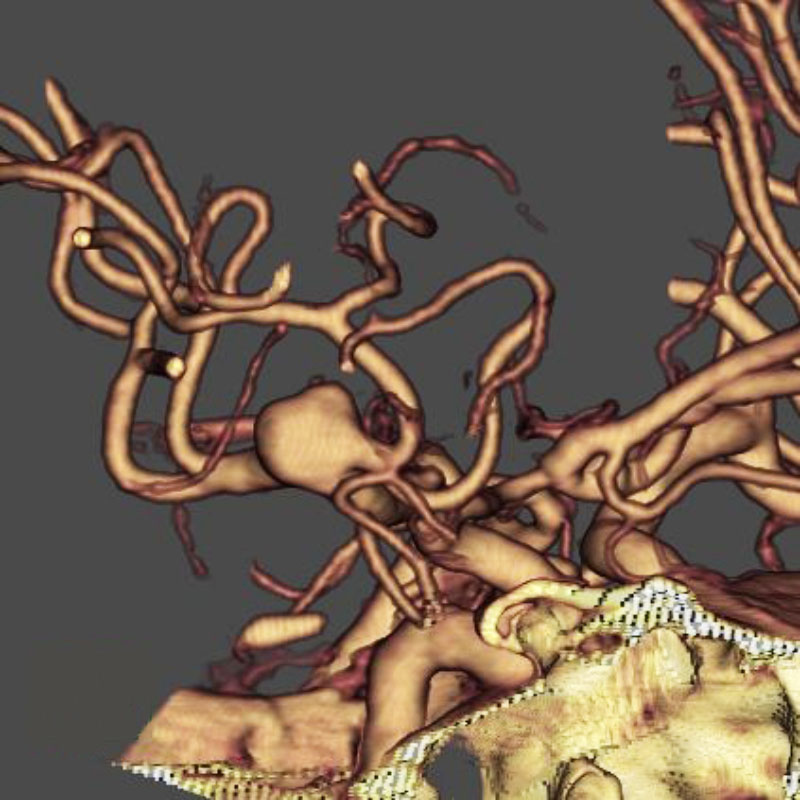

脳動静脈奇形

血管塞栓術

松田/濵田/元永